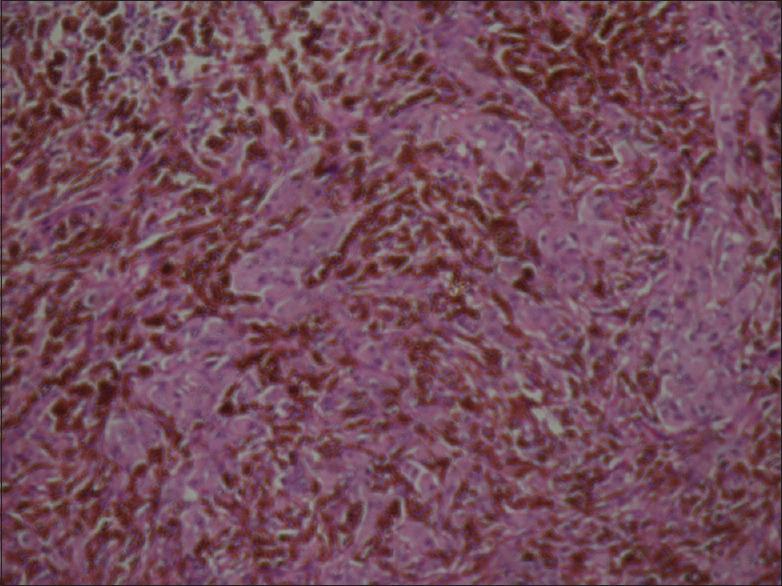

牙龈恶性黑色素瘤:病例报告及文献综述

Mucosal malignant melanoma arising from the head and neck region is a rare entity, and it is more aggressive than cutaneous melanoma. Furthermore, the complexity of the oral cavity makes surgical excision more difficult. Oral malignant melanoma is a rare tumour of melanocytic origin, accounting for 20-30% of malignant melanomas at the mucosal surface and 16% intra-orally. Hard palate and maxillary gingiva are the most common involved sites. The age of reported patients ranges from 20 years to 80 years. Hence, we do hereby present a case of malignant melanoma of mandibular gingiva with review of the literature in a 42-year-old female patient.

头颈部黏膜恶性黑色素瘤是一种罕见的疾病,且比皮肤恶性黑色素瘤更具侵袭性。此外,口腔的复杂性使得手术切除更加困难。口腔恶性黑色素瘤是一种罕见的黑素细胞起源肿瘤,占黏膜表面恶性黑色素瘤的20%-30%,口腔内占16%。硬腭和上颌牙龈是最常受累的部位。报告患者的年龄范围为20岁至80岁。因此,我们在此报告一例42岁女性下颌牙龈恶性黑色素瘤病例,并复习相关文献。